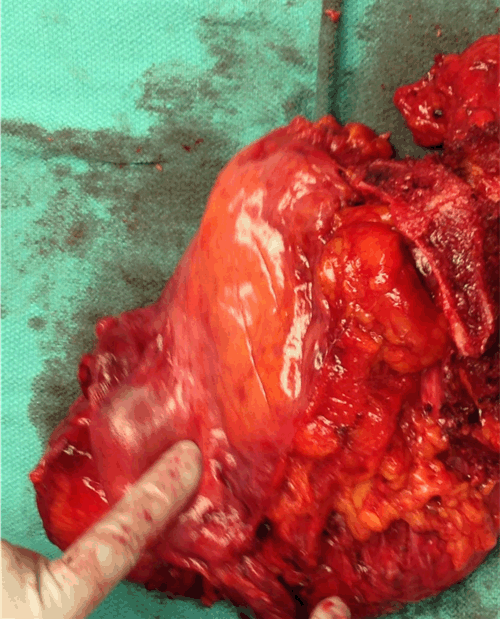

The patient was referred to gynecologic oncology for further evaluation. Pelvic examination demonstrated a 4-cm mass replacing the anterior distal vaginal mucosa and urethra. On pelvic MRI scan, a lobulated soft tissue mass measuring 2.4x1.8x2.9 cm extending from the posterior wall of the left vaginal fornix and prolapsing inferiorly into the vaginal canal was present. The mass appeared to infiltrate into the left vaginal forniceal wall superiorly (Figure 1). Whole body PET scan demonstrated an intensely hypermetabolic left anterolateral vaginal lesion measuring 2.8x2.1 cm consistent with a neoplastic process with no inguinal or pelvic lymphadenopathy.

Figure 1: Contrast-enhanced magnetic resonance imaging scan of pelvis, T2-weighted image demonstrating hyperintense mass measuring approximately 2.4x1.8x1.9 cm extending from the posterior wall of the left vaginal fornix.